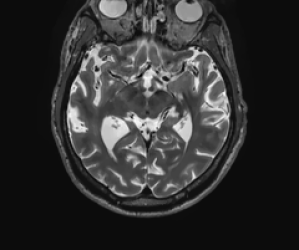

In our first experiment we perform multi-contrast MRI reconstruction from undersampled data. Since all contrasts are likely to share a structural information, less data is needed if the expected redundancy is exploited. Here we assume that a T2-weighted has been acquired using ”full data” and reconstructed without artefacts. We then use this image to reconstruct a T1-weighted image using only a fraction of the data. In this experiment we simulate the k-space data based on reconstructions of fully sampled clinical data.

The forward operator is a discrete Fourier transform defined on complex-valued images of size 256×256256256256\times 256, followed by a sampling operator corresponding to 15 equidistant spokes and a low-pass sampling of the 10×10101010\times 10 center of the k𝑘k-space. This yields a sampling of approximately 3%percent33\% of the k𝑘k-space. This sampling is easy to approximate on any clinical MRI scanner. The noise modelling here is Gaussian which is why we use the squared Euclidean norm (3) as data fidelity. The image domain is [1,1]2superscript112[-1,1]^{2} which corresponds to a pixel width of approximately 0.00780.00780.0078. The deformation field in this simulation is a rigid transform followed by zooming, given by

ϕzoom(x)=αRθx+bsubscriptitalic-ϕzoom𝑥𝛼subscript𝑅𝜃𝑥𝑏\displaystyle\phi_{\texttt{zoom}}(x)=\alpha R_{\theta}x+b

where Rθsubscript𝑅𝜃R_{\theta} is a rotation matrix (12) with angle θ=0.1𝜃0.1\theta=0.1, b=(0.02,0.08)T𝑏superscript0.020.08𝑇b=(-0.02,-0.08)^{T} is a translation vector, and α=0.85𝛼0.85\alpha=0.85 is a zoom factor. The latter means that the size of the side information image is only 85%percent8585\% of the size of the image which underlies the k𝑘k-space data. Since nonnegativity is not a meaningful assumption for complex-valued images, we drop this constraint in (10) for this test case. The resolutions and regularization parameters in Algorithm 2 were chosen as nk=(322,622,1282,2562)subscript𝑛𝑘superscript322superscript622superscript1282superscript2562n_{k}=(32^{2},62^{2},128^{2},256^{2}) and αk=5103(53,52,5,1)subscript𝛼𝑘5superscript103superscript53superscript5251\alpha_{k}=5\cdot 10^{-3}\cdot(5^{3},5^{2},5,1). For the TVTV\operatorname{TV} reconstruction we used αk=5104(53,52,5,1)subscript𝛼𝑘5superscript104superscript53superscript5251\alpha_{k}=5\cdot 10^{-4}\cdot(5^{3},5^{2},5,1). Here, and also for the following experiments, the resolutions were determined by successively dividing the resolution of the side information by a factor of two. The regularization parameters at the target resolution were chosen experimentally in order to maximize SSIM. Typically, the regularization parameter of TVTV\operatorname{TV} has to be chosen one or two orders of magnitude smaller than the one for dTVdTV\operatorname{dTV}.

The first row of Figure 3 shows the sampling pattern and the deformed image which was used to generate the data. Furthermore, it shows the side information and the ground truth image which we would like to reconstruct.

In the second row of Figure 3 we show the zero-filled reconstruction (pseudo-inverse), a standard TVTV\operatorname{TV} reconstruction, the result of the three-step method (22), and our proposed method. Obviously the pseudo-inverse and TVTV\operatorname{TV} method yield unsatisfactory results since the do not utilize the side information. Furthermore, they visualize the strong degree of ill-posedness of the problem where the sampled Fourier data alone cannot be used for a meaningful reconstruction. In contrast, both the three-step method (22) and our proposed method successfully correct the deformation between side information and data and yield good reconstructions despite the high degree of undersampling in the data. Notably, the proposed method yields better reconstructions of fine structures as can be seen in the zooms of Figure 3.

The previous observations are also supported by quantitative metrics. The SSIM values between the pseudo-inverse and TVTV\operatorname{TV} reconstruction and the deformed ground truth image which underlies the data are very low which is due to the strong undersampling. In contrast, the three-step method and the proposed method have high similarity values with the ground truth image, with slightly better numbers of the proposed method. Also the relative difference between the estimated affine deformation parameters and the ground truth parameters is lower for the proposed method than for the three-step method which underlines the superiority of our joint approach over the three-step method (22) in this application. We suspect that worse estimation of the deformation field of the three-step method is due to the fact that it must utilize the blurry and blocky TVTV\operatorname{TV} reconstruction for registration whereas the proposed method iteratively improves registration and reconstruction.